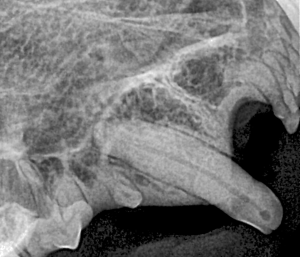

Canine Full Mouth Radiograph Example